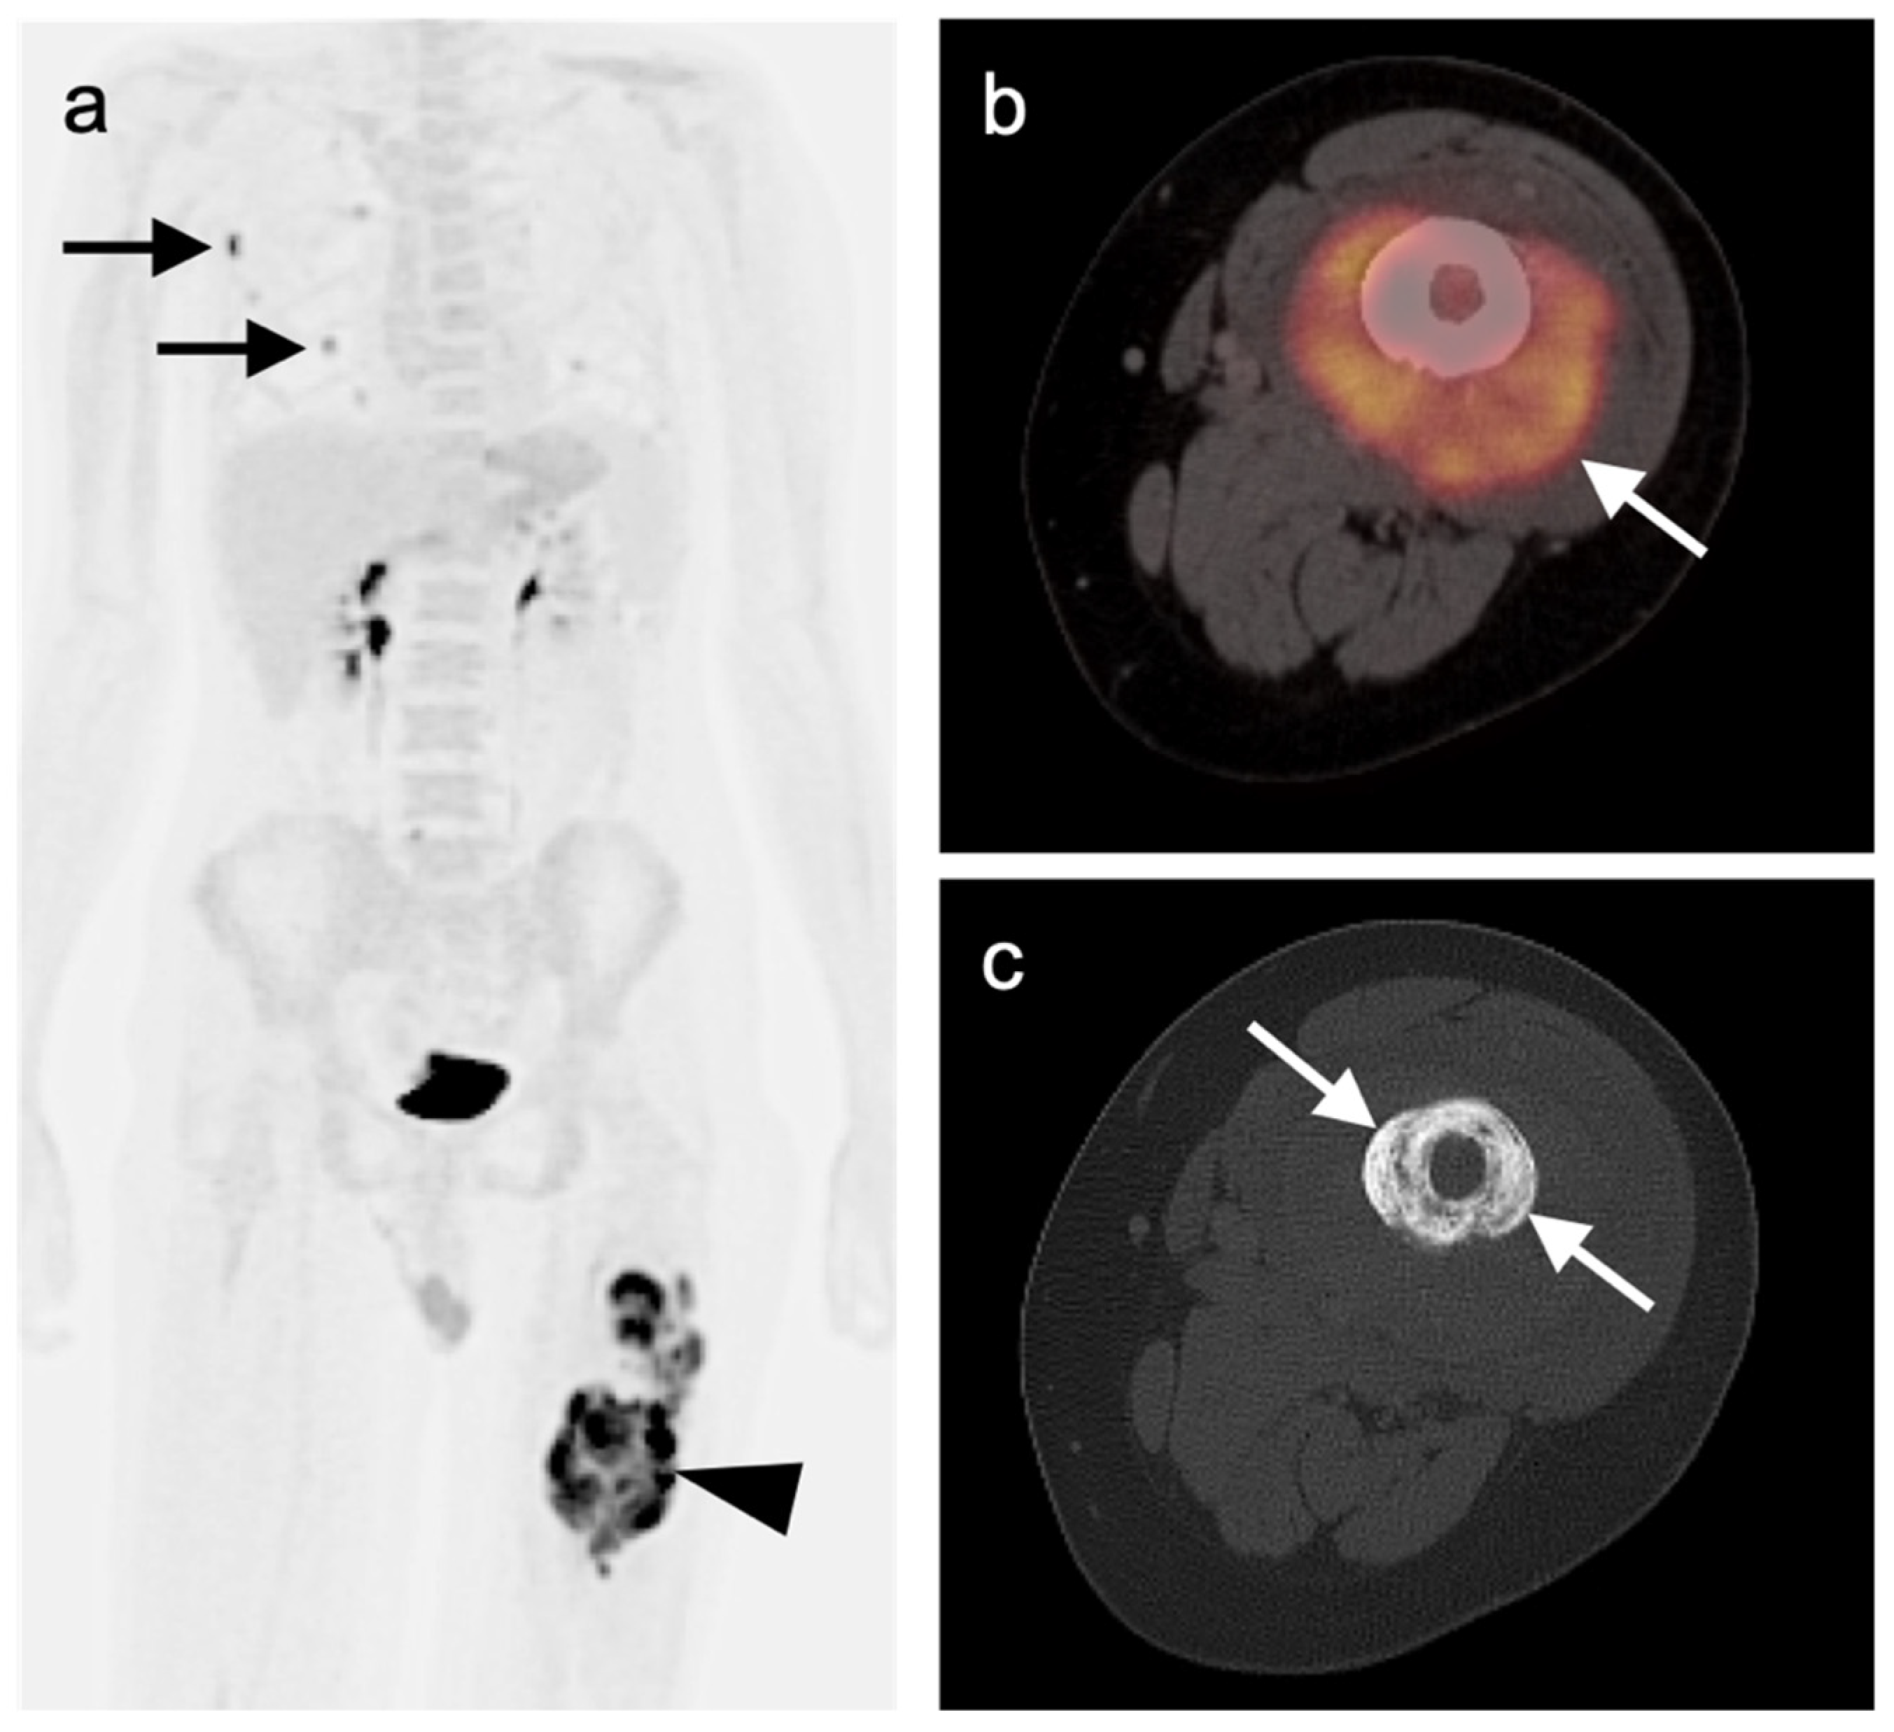

3.1.6. Liposarcoma

3.2.1. Chondrosarcoma

3.2.2. Osteosarcoma